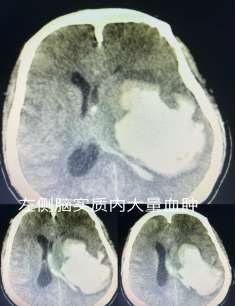

2024年4月一个普通的早晨,一阵急促的救护车在路上疾驰,伴随响亮的呼啸声传来,潢川县妇幼保健院 潢川二院急诊科严阵以待,前期已接到院前救治医生传来消息:“中年男性,发现昏迷2小时余,考虑脑卒中”。到院后立即开通绿色通道,急诊CT提示:左侧大脑半球大量出血,并破入脑室。神经外科主任熊海舰主治医师接到急会诊电话后,立即放下手上工作,快速前往急诊科给予会诊,见患者深昏迷,双侧瞳孔等大等圆,对光反射灵敏,无大小便失禁,但是GCS评分只有6分。考虑到患者虽然昏迷时间长,出血量大,但是患者并无脑疝现象,而且年轻无基础病,经积极救治后仍应有良好预后,充分评估病情后向家属告知病情,家属救治意愿积极,表示全力救治。

由于我院开通绿色通道,大大节省了术前准备时间,神经外科主任熊海舰提前联系手术麻醉科,沟通患者病情,做到患者入院后的无缝衔接,从入院到进入手术室仅仅用时30分钟,患者经过去颅骨骨瓣减压术+颅内血肿清除术等手术治疗后,颅内压明显降低,脑实质压迫解除,复查头颅CT血肿清除满意,无继发性出血,战斗取得了前期的胜利,术后3天患者苏醒,第4天拔除气管插管,第7天返回病房继续治疗,后期患者经积极治疗,历经出血、感染、下肢血栓、营养不良、康复训练等等考验,并择期行颅骨修补后,病情得到了进一步的恢复,已恢复自理能力,仅有少量言语障碍。潢川县妇幼保健院 潢川二院神经外科用其快速的反应、精湛的技术、完美的配合打了一个个漂亮的战斗,挽救了一个个家庭。